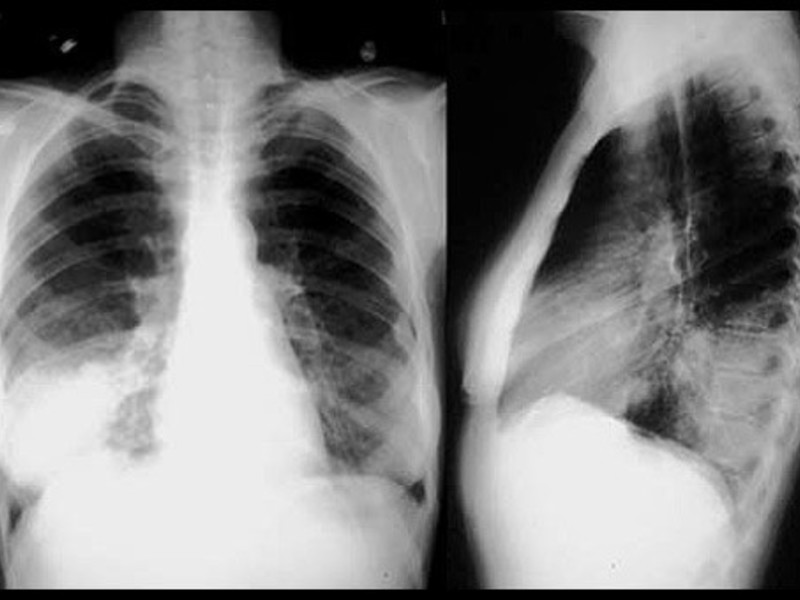

Очаговая пневмония на рентгене

Очаговая форма болезни проявляется легким лейкоцитозом, незначительными хрипами при дыхании и гипертермией. На начальном этапе развития заболевания его следы можно не обнаружить на рентгеновском снимке. Однако, опытный доктор может заподозрить заболевание по следующим косвенным признакам, видимым на снимках:

- Наличие теней.

- Признаки плеврита на рентгене.

- Увеличение размеров корня легкого.

- Нарушение структуры рисунка легочной ткани.

Проще всего пневмония на снимке выявляется в разгар болезни. На снимках становятся отчетливо видны очаги воспаления в виде темных пятен. Воспалительный процесс выгоняет из легочной ткани воздух, что делает ее более плотной. Появляются следующие признаки болезни:

- Отчетливые инфильтраты.

- Тени приобретают нечеткие контуры.

- На стороне пораженной доли легкого в плевре возможно появление жидкости, которая отлично видна на снимках.

На стадии выздоровления признаки заболевания на рентгене постепенно уходят:

- Исчезают инфильтраты.

- Признаки жидкости в плевре исчезают.

Стоит отметить, что даже после выздоровления на рентгене в течение нескольких месяцев все еще будет наблюдаться деформация рисунка легочной ткани.